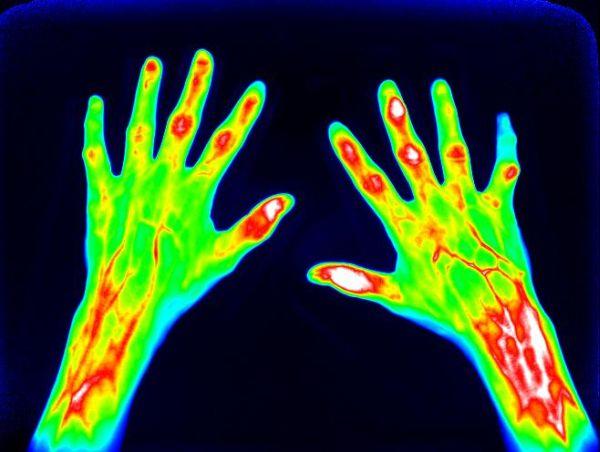

Münster (upm) - Es ist ein komplexer und zugleich beeindruckender Prozess, den der Körper bei Entzündungen in Gang setzt. Die Hauptrolle dabei spielen Immunzellen, die sich aus dem Blut ins Gewebe aufmachen, um die Entzündung zu bekämpfen. Sind zu viele dieser Zellen aktiv, können sie umgekehrt aber auch Schaden anrichten. Mehr über ihr Verhalten herauszufinden, kann Wissenschaftlern als Basis dafür dienen, individuelle Entzündungstherapien zu entwickeln – zum Beispiel Zellen zielgerichtet an den Entzündungsherd zu leiten oder eine Therapie rechtzeitig wieder abzusetzen. Forscher des Exzellenzclusters „Cells in Motion“ der Universität Münster haben nun eine Methode entwickelt, mit der sie die Aktivität von Entzündungszellen in Mäusen besser beurteilen und untersuchen können: Sie schafften es, Vorläufer von Immunzellen genetisch zu verändern, anschließend im Reagenzglas zu vermehren und im lebenden Organismus mit verschiedenen Bildgebungsverfahren zeitlich und räumlich zu verfolgen. Dabei arbeiteten Immunologen und Spezialisten für molekulare Bildgebung interdisziplinär zusammen. Mit der neuen Methode können zudem Tierversuche deutlich reduziert werden. Die Studie ist in der Fachzeitschrift „Theranostics“ erschienen.Die Geschichte im Detail:Wenn der Körper einen Infekt abwehrt, sind es zunächst verschiedene Arten von „Fresszellen“, sogenannte Phagozyten, die nacheinander aus den Blutgefäßen ins Gewebe zum Entzündungsherd wandern. Sie erkennen Krankheitserreger, „fressen“ sie und töten sie ab. Unkontrolliert aktiviert können sie andererseits auch dafür verantwortlich sein, dass Krankheiten voranschreiten. Um die Wanderungsmechanismen von verschiedenen Phagozyten zu erforschen, untersuchen Wissenschaftler meist genetisch veränderte Mäuse, die entzündliche Krankheiten aufweisen. Das ist allerdings nicht einfach, da man hierfür eine große Anzahl an Immunzellen benötigt und viele Mäuse als Spendertiere gezüchtet werden müssen. Mit ihrem neuen Ansatz lösten die Immunologen um Prof. Johannes Roth, Gruppenleiter am Exzellenzcluster, nun dieses Problem: Sie nutzten immortalisierte Vorläufer von Knochenmarkszellen, die ERHoxb8-Zellen, welche sich im Reagenzglas nahezu unendlich vermehren und unter bestimmten Bedingungen zu Immunzellen ausdifferenzieren. So erhielten die Forscher am Ende eine hohe Anzahl verschiedener Typen von Phagozyten.„Unser nächstes Ziel war es, genetische Veränderungen der Zellen zu erzeugen, wie sie zum Beispiel bei angeborenen Immundefekten auftreten“, sagt Johannes Roth. Solche Mutationen betreffen häufig Proteine in den Membranen von Immunzellen, die ihnen dabei helfen, zum Entzündungsort zu gelangen. Eines dieser Proteine ist das VLA4. Was genau passiert, wenn es fehlt, können Wissenschaftler aber nur eingeschränkt untersuchen, weil sie die notwendigen Mäusestämme nur sehr schwer züchten können. Auch hierfür fanden die münsterschen Immunologen eine Alternative im Reagenzglas: Sie nutzten das molekularbiologische Verfahren der Genom-Editierung, um mithilfe von Enzymen den für das VLA4 relevanten Genabschnitt in den Knochenmarksvorläuferzellen gezielt „auszuschneiden“ und entsprechende „defekte“ Immunzellen zu erzeugen. „Durch unsere neue Methode können wir nun erstmals verschiedene Arten von Immunzellen beliebig genetisch verändern und wichtige Entzündungsmechanismen ausschalten“, sagt Dr. Sandra Gran, eine der beiden Erstautorinnen der Studie.Bildgebung mit optischen und nuklearmedizinischen Verfahren Die Bildgebungsspezialisten um Nuklearmediziner Prof. Dr. Michael Schäfers, Koordinator des Exzellenzclusters, markierten die so gewonnenen Zellen mit verschiedenen fluoreszierenden Farbstoffen, um sie in lebenden Organismen zu untersuchen – zunächst mit dem optischen Verfahren der Fluoreszenz-Reflektions-Bildgebung. Sie injizierten Mäusen mit einer entzündungsbedingten Hautkrankheit sowohl mutierte als auch gesunde Immunzellen und schafften es, die Wege der Zellen jeweils innerhalb desselben Tiers zu vergleichen. Dadurch konnten sie die Zahlen der Versuchstiere deutlich senken, denn normalerweise müssen für solche vergleichenden Untersuchungen verschiedene Gruppen von Tieren eingesetzt werden. Die neue Methode funktionierte: „Wir konnten sehr genau beobachten, wie unterschiedlich sich die verschiedenen Immunzellen verhielten. Zum Entzündungsherd schafften es etwa doppelt so viele gesunde Immunzellen im Vergleich zu den genetisch veränderten“, sagt Dr. Lisa Honold, ebenfalls federführende Autorin der Studie. Auf dieselbe Weise untersuchten die Forscher mit ihrem neuen Verfahren noch weitere Zellen, denen andere Membranproteine fehlten. In einem weiteren Schritt sahen sich die Wissenschaftler wandernde Immunzellen in Mäusen mit einem Herzinfarkt an. Solche Untersuchungen stellen naturgemäß eine große Herausforderung dar, da das Herz tief im Körperinneren liegt und sich beim Pumpen sehr schnell bewegt. Die Forscher nutzten ein nuklearmedizinisches Bildgebungsverfahren, mit dem sie digitale Schnittbilder aus tiefen Gewebeschichten herstellen können: die Einzelphotonen-Emissions-Tomographie, SPECT genannt. Sie markierten die Zellen im Reagenzglas mit einer radioaktiven Substanz, deren Strahlung gemessen und in Bildern sichtbar gemacht werden kann. Nachdem sie die Zellen Mäusen injiziert hatten, untersuchten sie, wo sich die markierten Zellen in verschiedenen Phasen des Infarkts aufhielten. „Durch die serielle Bildgebung können wir nun das Verhalten von Immunzellen über einen langen Zeitraum verfolgen“, sagt Nuklearmediziner Michael Schäfers. Auch das soll dazu führen, die Zahlen der Versuchstiere zu senken, weil herkömmliche molekularbiologische Methoden lediglich Momentaufnahmen liefern und weitaus mehr Experimente erfordern.Die Wissenschaftler wollen ihre neue Methode auch in Zukunft in präklinischen Untersuchungen anwenden und weiterentwickeln – beispielsweise bei Infektionen, rheumatologischen und arthritischen Erkrankungen. Wann die Ergebnisse für patientenorientierte Anwendungen relevant sind, ist allerdings derzeit noch nicht absehbar.Die Studie entstand in einem interdisziplinären Flexible-Funds-Projekts von CIM. Darüber hinaus erhielt sie Mittel der WWU-Sonderforschungsbereiche 656 „Molekulare kardiovaskuläre Bildgebung“ und 1009 „Breaking Barriers“ sowie des Interdisziplinären Zentrum für klinische Forschung der Medizinischen Fakultät Münster. Das Bundesforschungsministerium förderte die Studie ebenfalls.Link zur Publikation